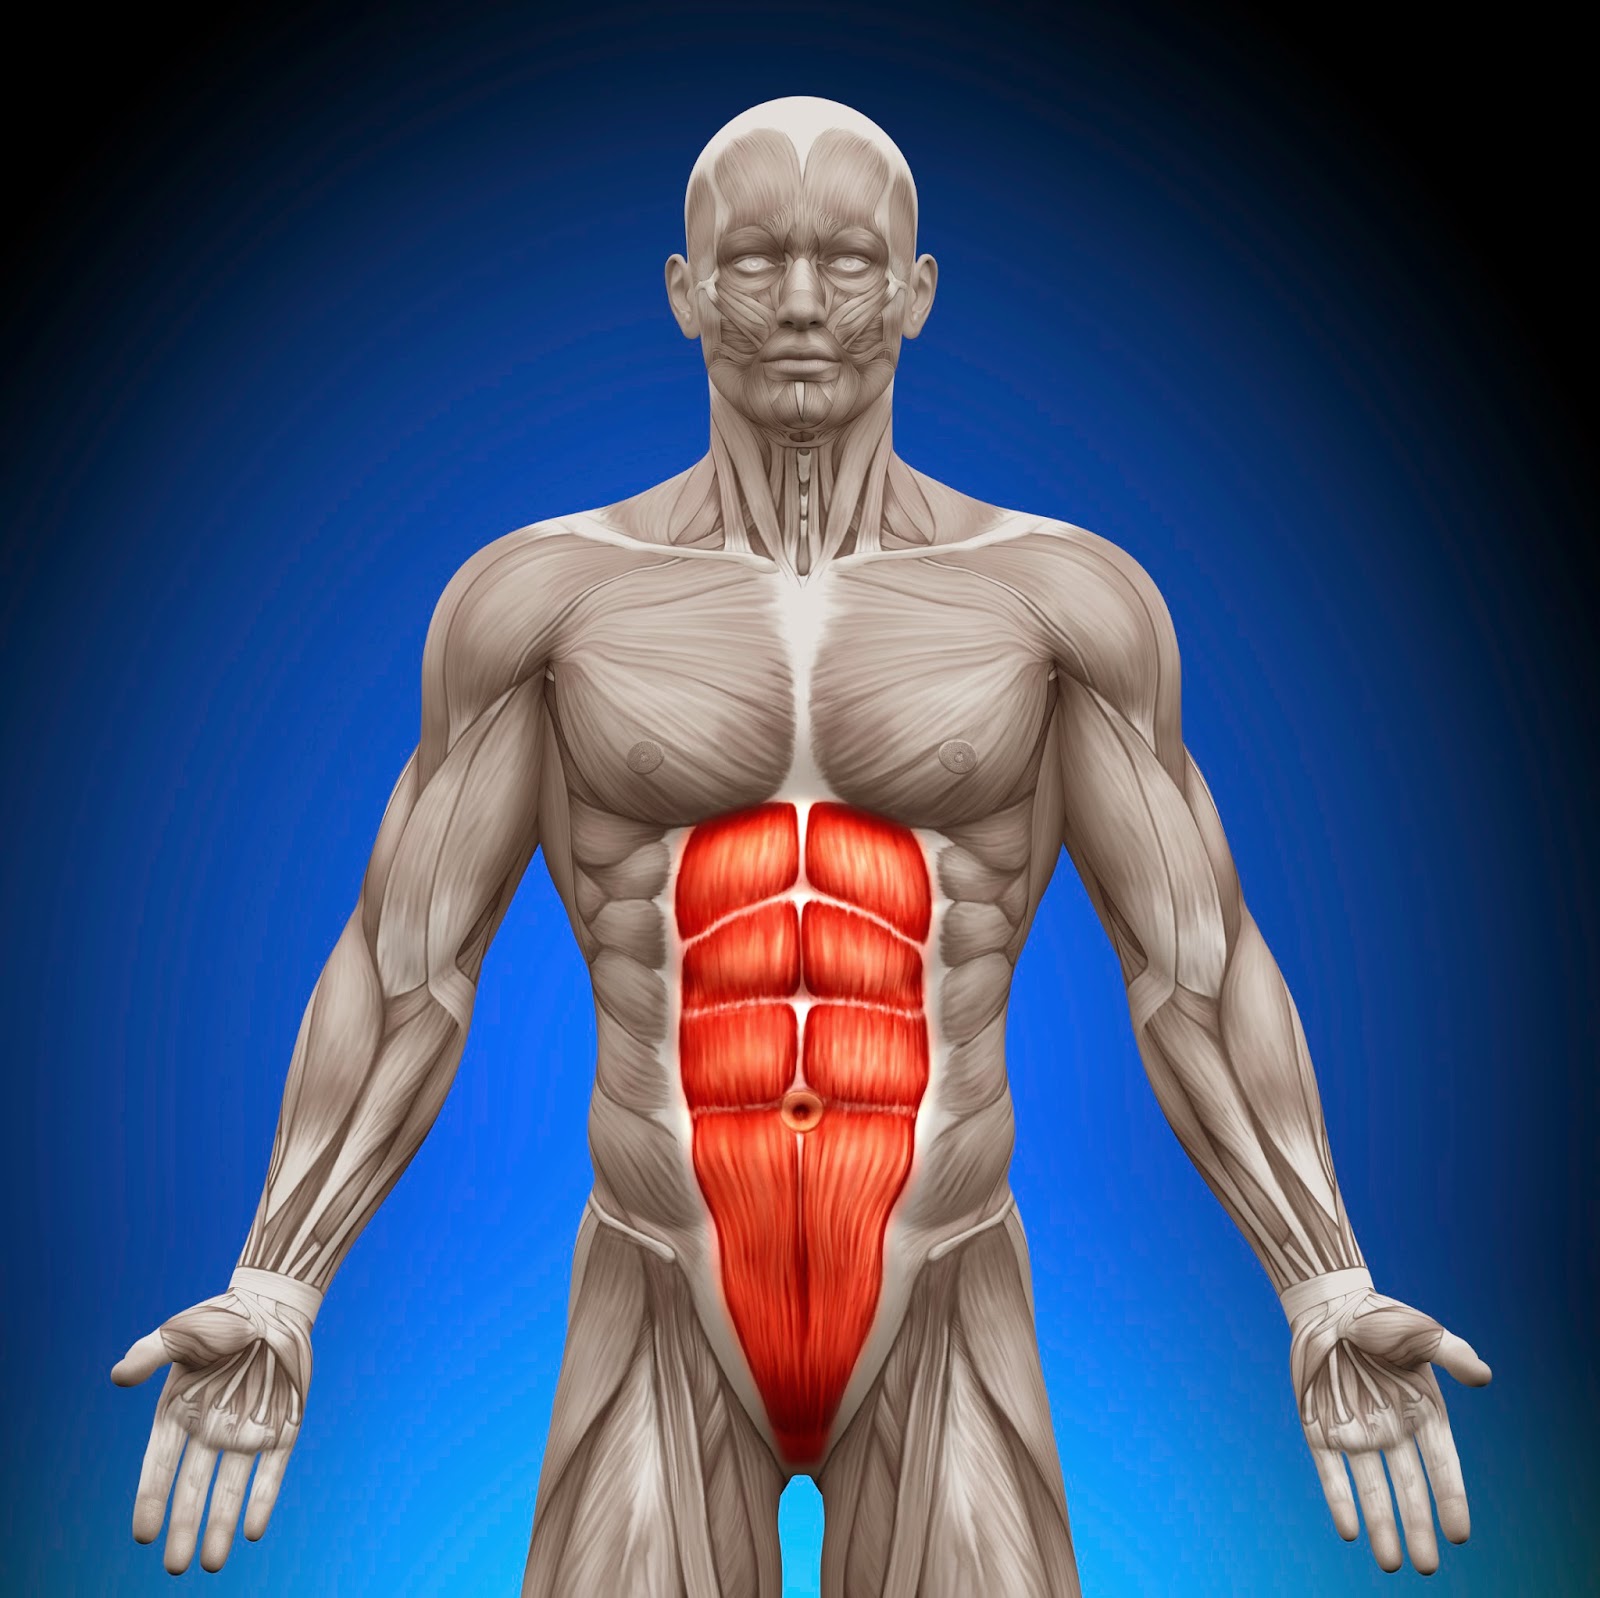

Abdominal Muscles Anatomy Muscle Anatomy Body Anatomy Human Anatomy

Body Facts The Abdominal Muscles And Their Function Fitness For Muscle